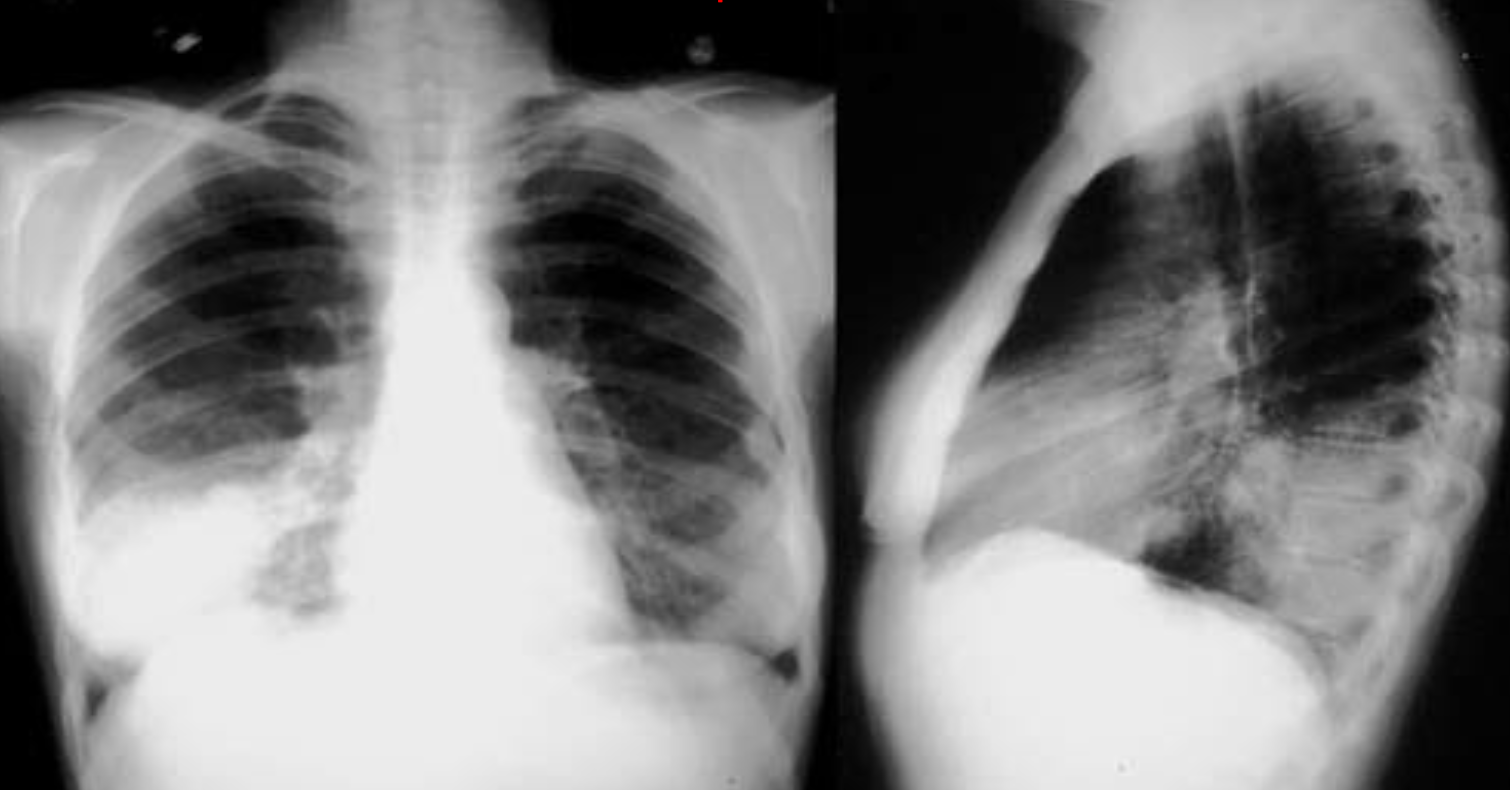

A. What is the most likely diagnosis in the given images; RT lower lobe pneumonia

B. Which lobe of the lung affected by this disease in the given image. Lower lobe, reverse change of opacity from spine

A. What is the most likely diagnosis in the given images

pneumonia ex… due fever cough and the imaging

B. Which lobe of the lung affected by this disease in the given image. Right middle Lobe Lesion, due obliteration of diaphragm - and lateral of horizontal fissure opaque